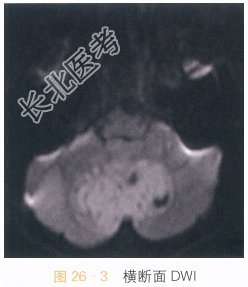

男,9岁,头痛4月余。

读片分析:头颅横断面T₁WI见小脑蚓部巨大软组织肿块影,呈不均质低信号,形态不规则,边界不清;横断面T₂WI可见病灶呈不均质高信号,周围可见瘤周水肿;增强扫描肿瘤部分可见不均质强化。